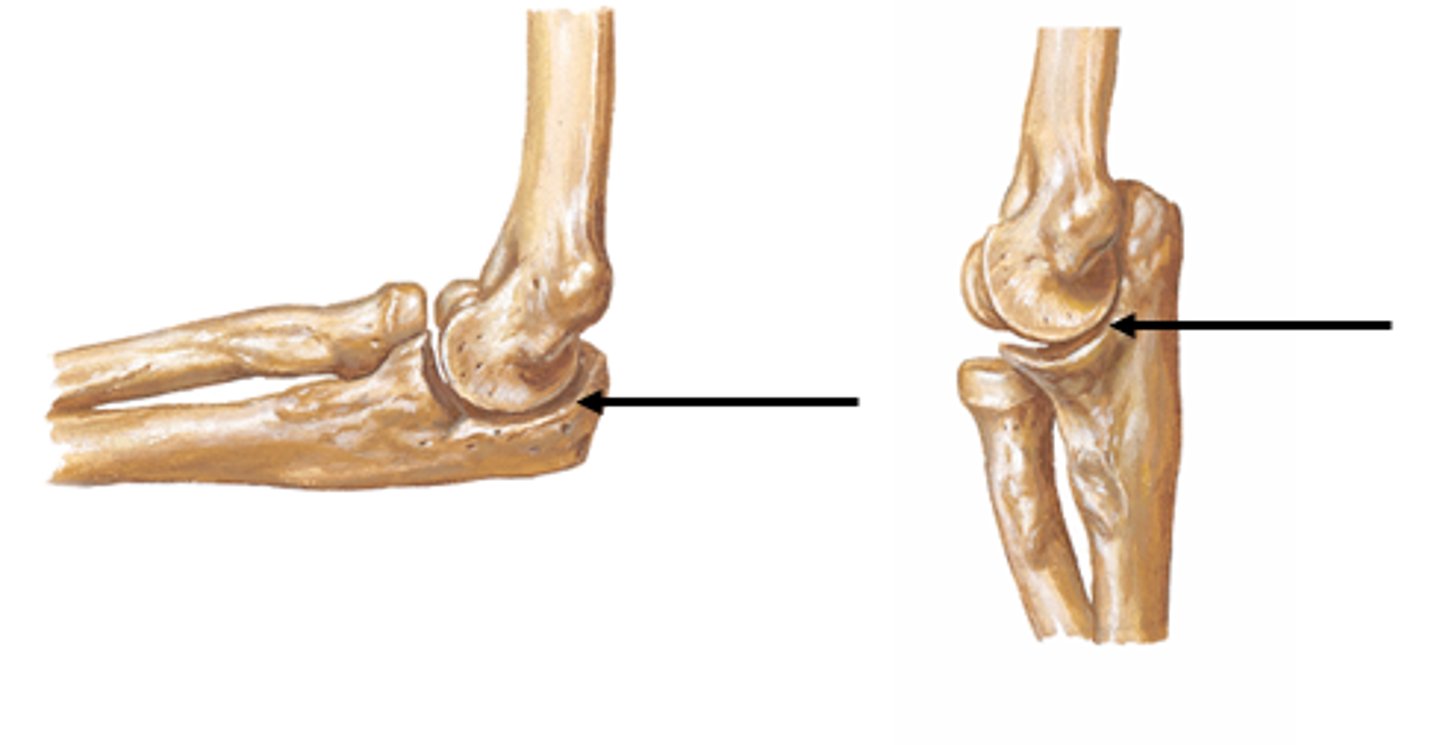

Olecranon of the ulna:

Superior, most proximal portion.

What does the olecranon of the ulna articulate with?

Articulate with olecranon fossa of the humerus on its

anterior side

What is the function of the olecranon of the ulna?

Serve as a short lever for extension of the elbow

Head of the radius:

Articulates with the capitulum of humerus and with the radial notch of the ulna